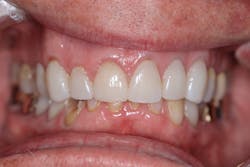

Take, for example, this 73-year-old male whose chief complaint was for his new dentist (me) to “keep doing what my other dentist was doing and fix the teeth that needed fixing.” The patient’s health history was benign, but dentally, he had the front six teeth crowned due to an accident he sustained while riding his bike. Following that, he was under the comprehensive care of a prosthodontist to restore his teeth, bite, and eliminate any issues that came about from grinding and wear.

Radiographically, the first thing I noticed were the tabletopped occlusal surfaces (figures 1 and 2). Clinically, the same was evident, along with generalized wear facets on the posterior teeth (figures 3 and 4). The bite was deep (figures 5 and 6), and the lower anterior teeth had been worn down to half their original size. There were new ceramic crowns on nos. 21, 28, and 29. I also noted that there was an occlusal stop/resin on no. 13, but there was no significant effect on his occlusion as it was even on the right and left sides.